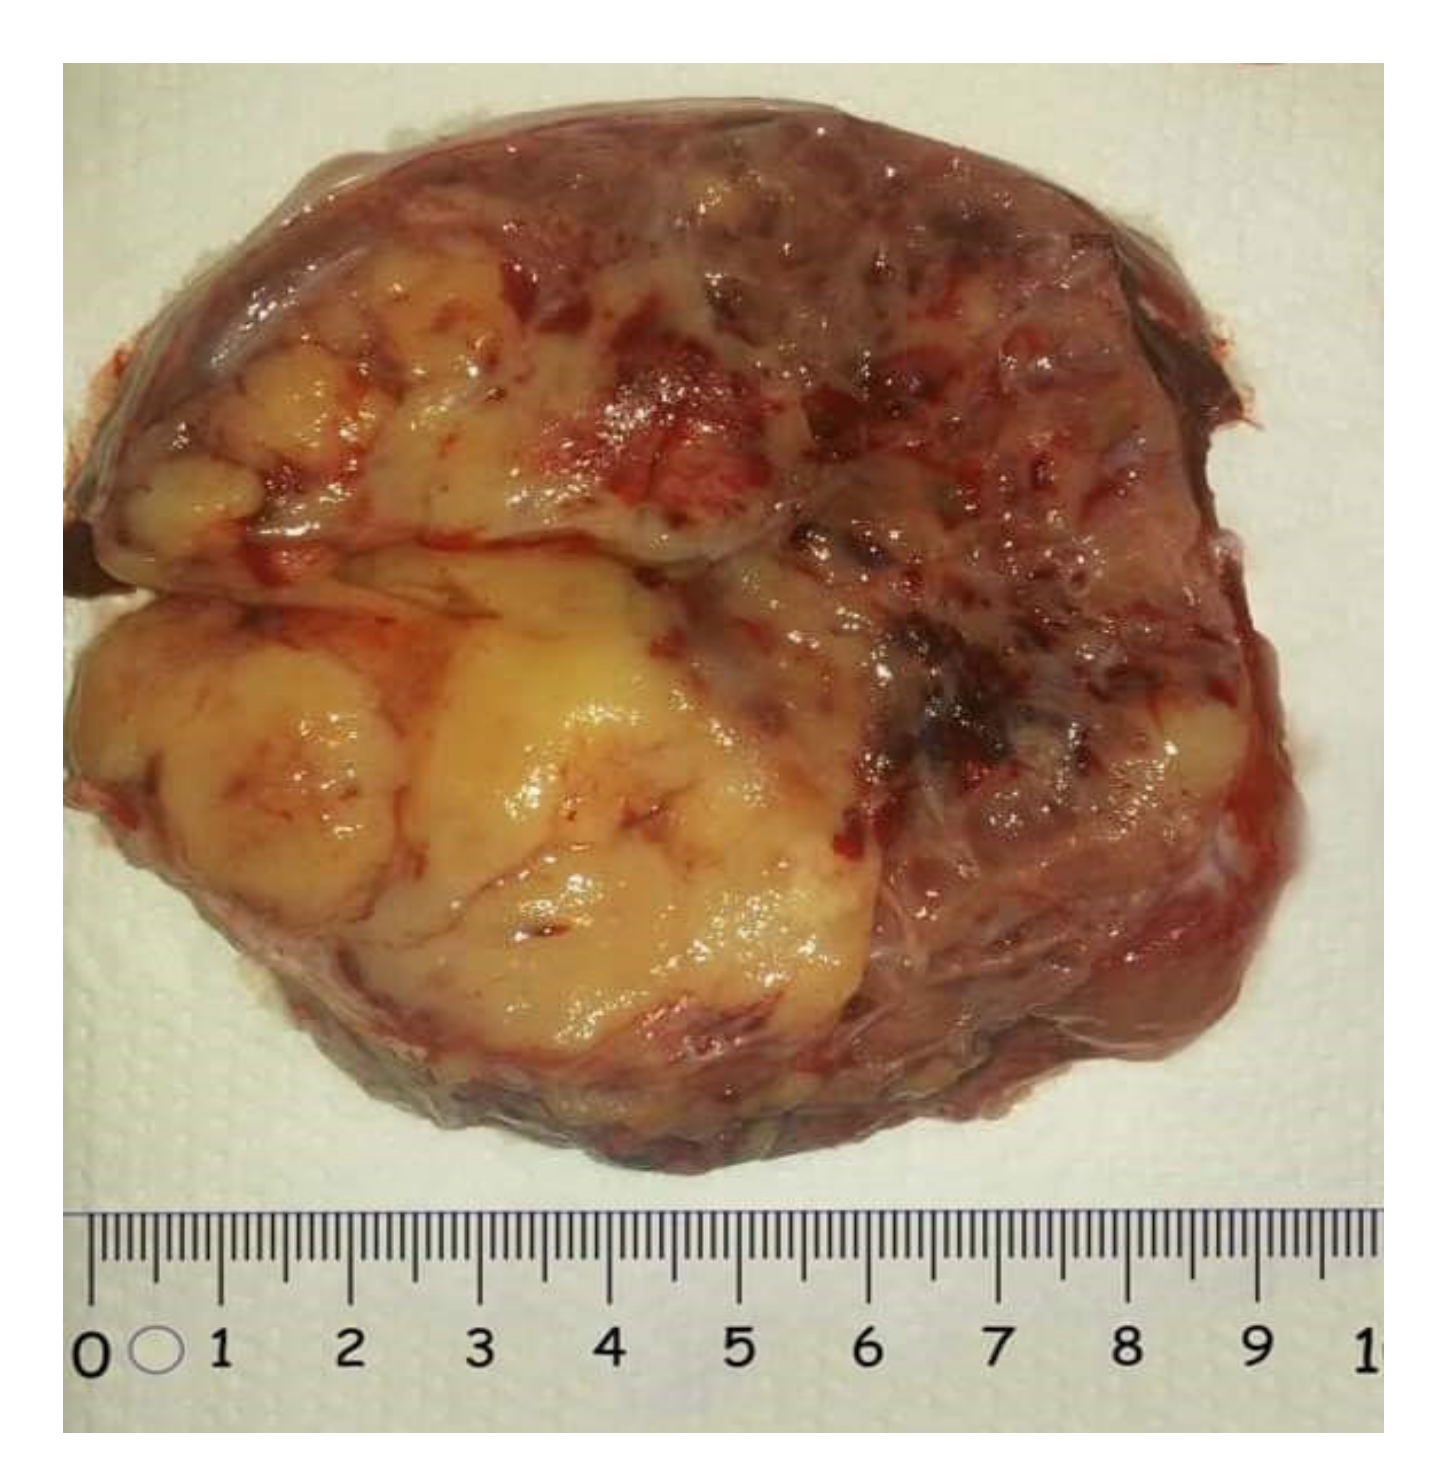

2.1.1. Macroscopic Features

2.3.1. Macroscopic Features